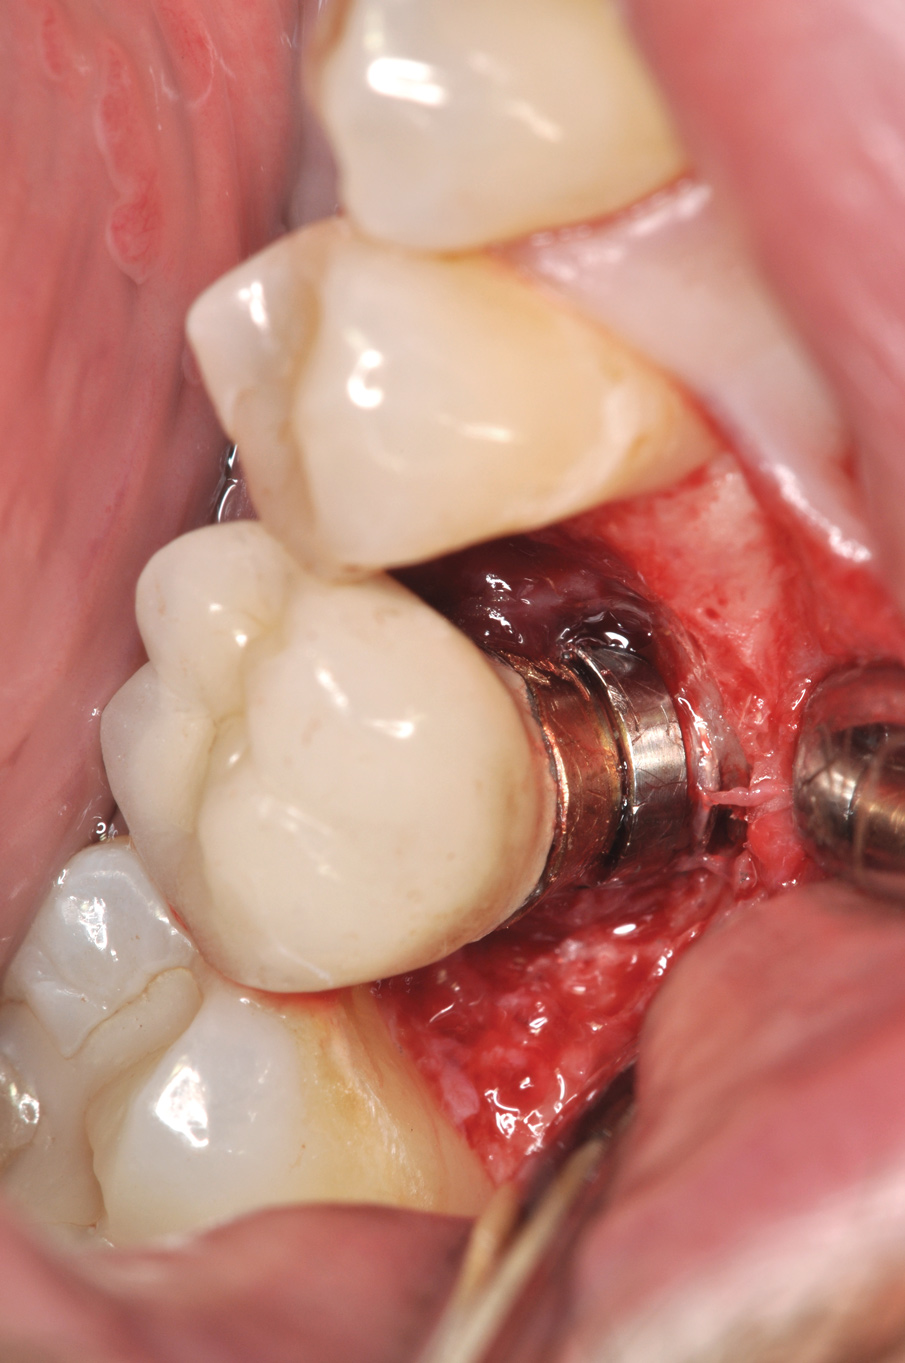

Fig 14. Clear resin cement left on the implant abutment.

Figure 14

Fig 15. Implant abutment following cement removal.

Figure 15

Excess Cement Leading to Peri-implantitis

If all implant-supported crowns could be designed for screw retention, no discussion of excess cement would be necessary. However, screw retention is not always possible depending on the location of the access opening and because of the unesthetic appearance in anterior restorations or the mesial/distal angulation of the implant compromising the path of insertion (Figure 12). Residual cement left after crown cementation on implants can lead to peri-implant inflammation, peri-implantitis, and eventual loss of the implant (Figure 13 through Figure 15).25 The presence of lingering excess cement can encourage the development of bacterial colonization and peri-implantitis. Conversely, when too little cement is used, voids in the cement layer can occur and the prosthesis can become loose.26 The deeper the implant crown margin, the more difficult it is to remove excess cement.27

Radiopaque cements that contain zinc phosphate and zinc oxide (with and without eugenol) should be considered to help identify excess interproximal cement; however, this should be used secondarily to proper margin height and careful removal of cement during cementation. Resin cements lack the same opacity as zinc-containing cements and have been shown to be the most difficult to remove.28 Often in the process of removing this excess cement, the abutment surface becomes scratched and damaged, potentiating further plaque accumulation.29